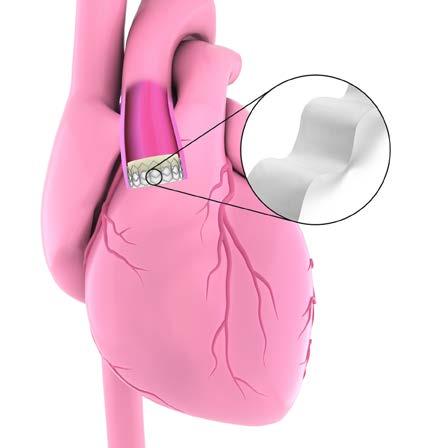

The rise in heart valve disease and other cardiovascular conditions has led to a growing demand for minimally invasive devices and technologies. In addition, medical devices need to meet specific tissue response and durability criteria for the biomedical structures to elicit proper biologic responses. This means that medical devices need to be small and flexible to enable minimally invasive surgeries while also being strong and durable so they can last for the full life of the patient. The use of ultra-high molecular weight polyethylene fibers like Honeywell Spectra® UF BIO can play a significant and useful role in the development of biocompatible medical devices, particularly in the field of cardiovascular applications such as heart valves.

Spectra® UF BIO Fiber is a product portfolio that falls under the Honeywell medical grade fibers offering that is known as Spectra® MG BIO Fibers. All of the products within the Spectra MG fiber portfolio are 100% ultra-high molecular weight polyethylene (UHMWPE) fibers. These fibers are manufactured through a unique gel spinning process — the first of its kind. It’s one of the world’s strongest and lightest fibers, enabling the design of medical devices that have higher surgical accuracy rates, faster recoveries, and better patient outcomes.

Ultra-fine UHMWPE fiber like Spectra MG is 15 times stronger than steel by weight, 40% stronger than aramids on a weight-byweight basis and three times stronger than polyester on a volume basis. It also offers high pliability, low elongation and a low coefficient of friction that allow the development of stronger, lowerprofile devices.

Strong, thin fiber ideal for lower profile devices

Smaller-profile medical devices are important especially for cardiovascular patients. They help facilitate less invasive procedures that reduce patient discomfort and recovery time. Honeywell’s Spectra UF BIO offers a stronger, thinner solution as compared to traditional materials such as nylon and polyester making it ideal for even the smallest cardiovascular devices. Available from 100 denier down to the 10 dtex, this UHMWPE fiber allows for smaller devices that can access smaller anatomical structures other devices can’t reach.

Spectra UF BIO can be shaped into a variety of textile constructions, including braids, woven shapes and knits to enhance the design of implantable cardiovascular devices. Spectra UF BIO is biocompatible, chemically inert and offers superior resistance to fatigue and abrasion compared to polyester – extending the life of in-body devices compared to those using a polyester fiber. This creates the potential for improved patient quality of life by reducing the need for revision surgeries in the future. Spectra UF BIO also has a lower coefficient of friction than polyester, resulting in easier transfer through tissue and enabling lower levels of patient inflammation after surgery.

Use of Spectra UF BIO in cardiovascular is just one of the many key areas that benefit from the use of this small, yet strong fiber. Spectra UF BIO can also be used in orthopedics, surgical robotics, and more.

Interested in learning more?

Customers have trusted Honeywell to solve their greatest challenges for more than a century, and we’re committed to helping innovate with you. Our lineup of medicalgrade fibers is produced at our world-class U.S. manufacturing sites and is backed by our strong technical support and expertise in UHMWPE.